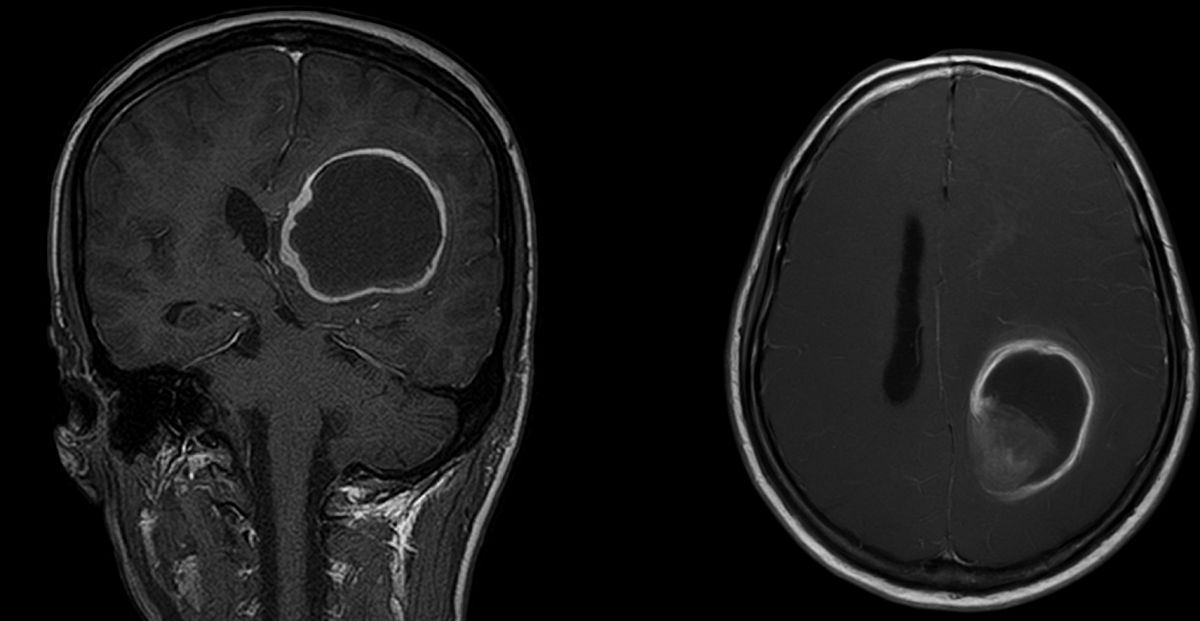

Nález na magnetické rezonanci u pacienta s bolestmi hlavy.

Diagnóza se obvykle stanoví pomocí magnetické rezonance s podáním kontrastní látky, která nádor na snímcích zvýrazní a pomůže odhalit jeho nepravidelnou strukturu. Definitivní potvrzení je však možné až po histologickém vyšetření vzorku tkáně, získaného při operaci nebo biopsii. V současnosti se nádory hodnotí nejen podle mikroskopického vzhledu, ale podle zmíněných molekulárních znaků, například přítomnosti nebo nepřítomnosti mutace v genu IDH. Tato informace je velmi důležitá, protože nádory s touto mutací mají často jiný průběh a obvykle i lepší prognózu. Proto hrají molekulární znaky klíčovou roli při přesném určení typu nádoru i při odhadu dalšího vývoje onemocnění.